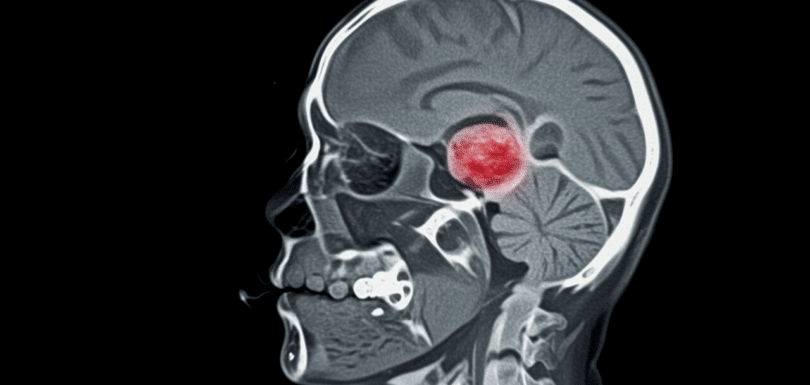

Head CT Stroke Hemorrhage Trauma Odessa TX

Head CT for Stroke, Hemorrhage, or Trauma Emergency Treatment in Odessa TX | Priority ER – 24/7 Head CT for stroke, hemorrhage, or trauma is a critical diagnostic test required immediately when experiencing sudden weakness, severe headache, altered consciousness, head injury, or neurological symptoms. Priority ER provides 24/7 emergency head CT imaging with zero wait […]